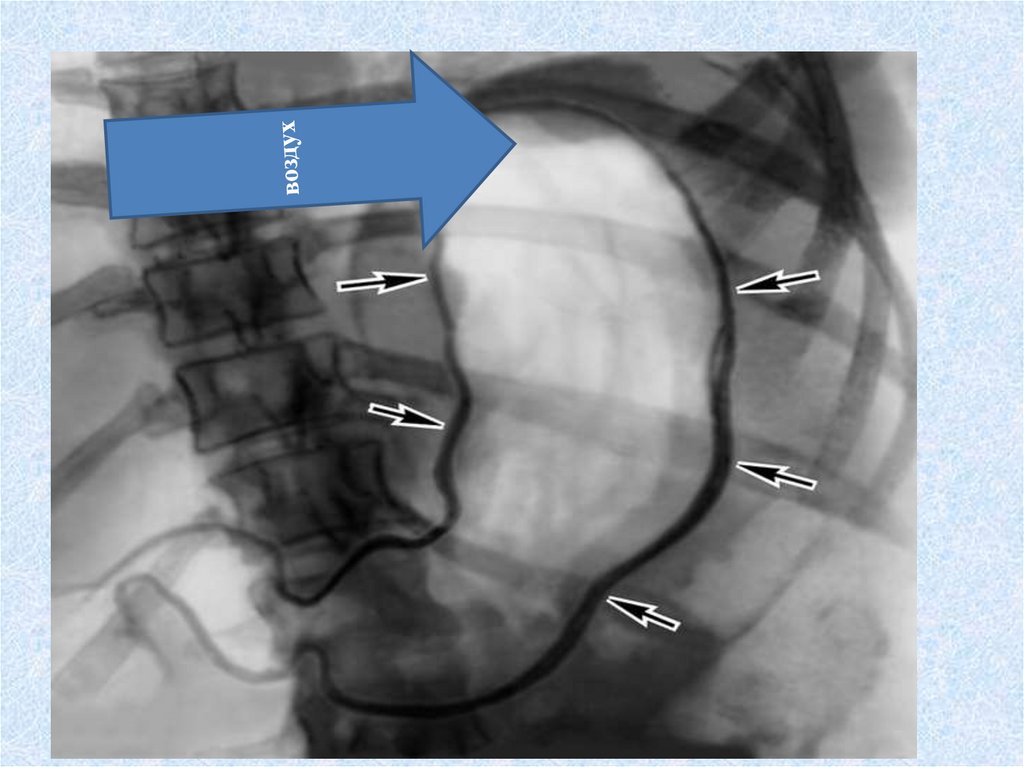

пищевод

Длина 25-30см

Диаметр 25мм

Соединяет глотку с желудком

от VI-VII v.c. до XI v. th

3 частишейная грудная брюшная

Сужения пищевода- 5

(3 анатомических+

2 физиологических)

ТРИ АНАТОМИЧЕСКИХ• В МЕСТЕ ПЕРЕХОДА ГЛОТКИ В ПИЩЕВОД

(ГЛОТОЧНОЕ)

• НА УРОВНЕ ДЕЛЕНИЯ ТРАХЕИ НА БРОНХИ

(БРОНХИАЛЬНОЕ)

• ПРИ ПРОХОЖДЕНИИ ПИЩЕВОДА ЧЕРЕЗ ДИАФРАГМУ

(ДИАФРАГМАЛЬНОЕ)

ДВА ФИЗИОЛОГИЧЕСКИХ АОРТАЛЬНОЕ – РЯДОМ ДУГА АОРТЫ, УРОВЕНЬ (VI v.th)

КАРДИАЛЬНОЕ- ПРИ ВХОДЕ В ЖЕЛУДОК

Функция пищеводаактивное продвижение

пищевого комка

за счет сокращений мышечной

оболочкиПЕРИСТАЛЬТИКА